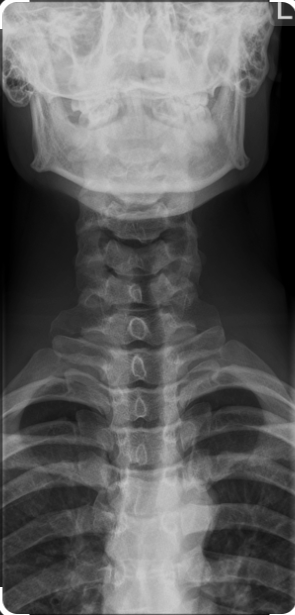

X-ray Cervical Spine AP View

About X-ray Cervical Spine AP View

If you’re looking for an affordable X-ray Cervical Spine AP View, Medifyhome partners with top NABL-certified diagnostic centers and clinics. This X-ray imaging procedure offers a comprehensive view of the cervical (neck) and dorsal (upper back) regions of the spine, helping to assess the bones, joints, and surrounding structures for abnormalities. Whether for injury, pain, or post-surgical evaluation, this imaging method is instrumental in guiding treatment and recovery plans.